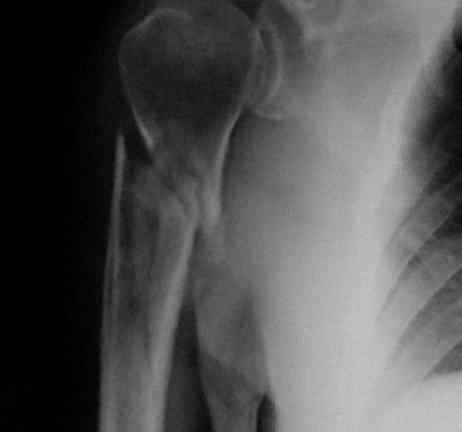

PRE – OPERATORIO

C3

POST – OPERATORIO